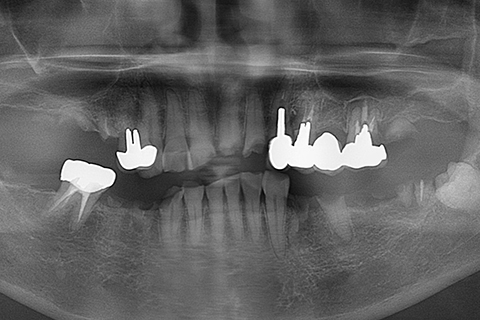

症例4

治療前

治療後

- 年齢・性別

- 60歳

- 治療期間

- 6ヶ月

- 抜歯

- 残根抜歯のみ

- 治療費

- 184.8万円

- 備考

- 右上5.6 右下5 左下4.5.6欠損

- 治療内容

- 6本のインプラントを右左側に2回に分けて埋入

- 施術の副作用(リスク)

- オペによる知覚障害。インプラントによる歯肉炎。インプラント脱落。